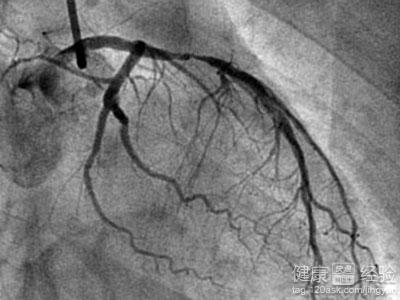

首先介紹一下冠心病造影,冠心病造影也被稱作冠脈造影或者冠狀動脈造影,是檢查冠心病,診斷冠心病目前最標准的一項檢查項目,而冠脈造影只是檢查,並沒有什麼治療效果的作用,並且檢查費用比較高,根據各地區的消費不等,一般冠脈造影的價格在3000到6000之間,如果您個人有醫療保險的話,會減少一部分費用,當然這些價錢還不加上住院的費用等等,所以得了冠心病的患者平時一定要注意,不然後面治療花費的費用將更多,做一個支架都得在9000以上,後面還要加上藥物的費用,住院的費用等等。所以,還是要多愛護自己的身體。

1首先,還是支持各位患者到大型的綜合醫院進行檢查治療,冠心病屬於心腦血管疾病的一種,冠心病史由於動脈粥樣硬化所導致的,而冠心病造影也被稱作冠脈造影或者冠狀動脈造影,是檢查冠心病,診斷冠心病目前最標准的一項檢查項目,而冠脈造影只是檢查,並沒有什麼治療效果的作用。

2其次,就是冠脈造影的價格,冠脈造影相對於其他較普通的檢查來說費用較高,而且只是檢查作業,並沒有治療的作用,根據各地區的消費不等,一般冠脈造影的價格在3000到6000之間,如果您個人有醫療保險的話,會減少一部分費用,當然這些價錢還不加上住院的費用等等